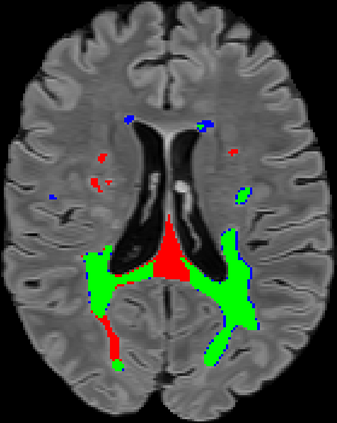

Recently, segmentation methods based on Convolutional Neural Networks (CNNs) showed promising performance in automatic Multiple Sclerosis (MS) lesions segmentation. These techniques have even outperformed human experts in controlled evaluation conditions such as Longitudinal MS Lesion Segmentation Challenge (ISBI Challenge). However state-of-the-art approaches trained to perform well on highly-controlled datasets fail to generalize on clinical data from unseen datasets. Instead of proposing another improvement of the segmentation accuracy, we propose a novel method robust to domain shift and performing well on unseen datasets, called DeepLesionBrain (DLB). This generalization property results from three main contributions. First, DLB is based on a large group of compact 3D CNNs. This spatially distributed strategy ensures a robust prediction despite the risk of generalization failure of some individual networks. Second, DLB includes a new image quality data augmentation to reduce dependency to training data specificity (e.g., acquisition protocol). Finally, to learn a more generalizable representation of MS lesions, we propose a hierarchical specialization learning (HSL). HSL is performed by pre-training a generic network over the whole brain, before using its weights as initialization to locally specialized networks. By this end, DLB learns both generic features extracted at global image level and specific features extracted at local image level. DLB generalization was validated in cross-dataset experiments on MSSEG'16, ISBI challenge, and in-house datasets. During experiments, DLB showed higher segmentation accuracy, better segmentation consistency and greater generalization performance compared to state-of-the-art methods. Therefore, DLB offers a robust framework well-suited for clinical practice.